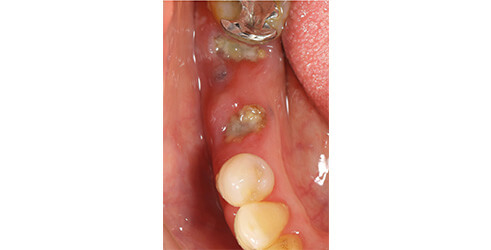

セラミックインレーの装着時には写真のようにラバーダムというゴムのシートを使うことにより接着力が増します。

接着力が増すと虫歯の再発率を減らすことにつながります。